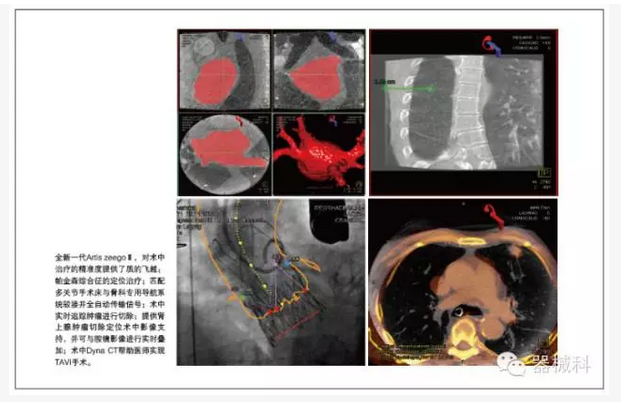

胸心外科是復(fù)合手術(shù)室的最重要使用科室之一。西門子在中國,在世界,都是心臟復(fù)合手術(shù)室技術(shù)的開創(chuàng)者和領(lǐng)先保持者。國內(nèi)著名的心血管病中心一直采用西門子復(fù)合手術(shù)室,并開創(chuàng)了心臟外科復(fù)合手術(shù)的“中國式經(jīng)驗”。在TAVI等治療上,西門子擁有獨特的軟硬件支持,特別是術(shù)中Dyna CT,可以幫助醫(yī)師實現(xiàn)TAVI手術(shù)。

在胸外科肺部腫瘤及肝臟腫瘤微創(chuàng)手術(shù)的治療最前沿,西門子復(fù)合手術(shù)室提供術(shù)中腫瘤定位等實用技術(shù)支持,通過實時的Dyna CT和術(shù)前MR圖像融合,包括超聲及術(shù)中腔鏡影像,來確定腫瘤的位置,并術(shù)中實時追蹤腫瘤進行切除。